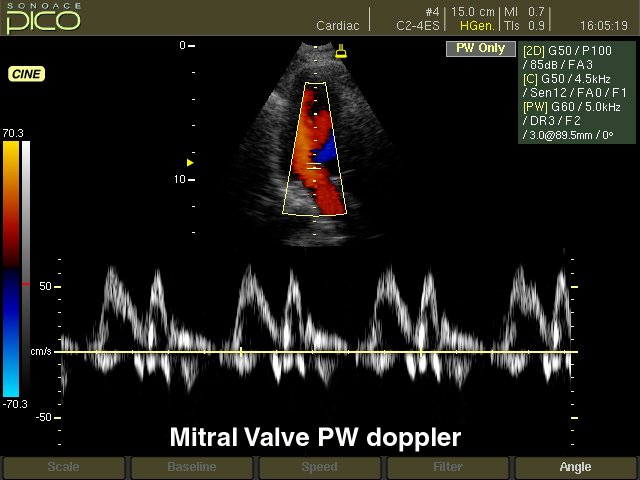

SonoAce Pico - портативный ультразвуковой аппарат компании Medison с цветным допплером и кардиопакетом для исследования сердца плода.

- CFM - цветное допплеровское картирование;

- PD - энергетический допплер;

- PW - импульсный допплер;

- дуплексный и триплексный режим; трапецевидный режим сканирования для линейных датчиков. - Кардиопакет для исследования сердца плода (входит в базовую комплектацию).

- Кардиологические измерительные программы: оценка митрального и аортального клапанов; оценка левого желудочка по формулам CUBED, POMBO, TEICHHOLZ и в B-режиме: ESP, EBP, BUL, MSR.